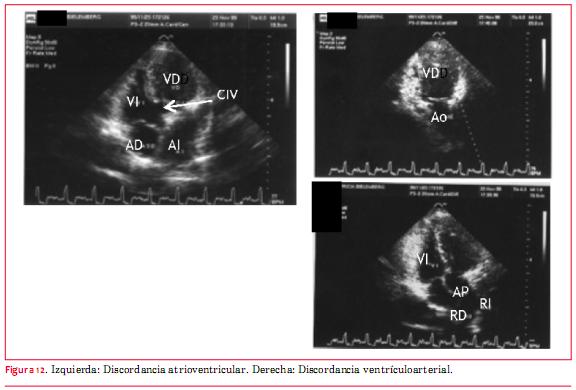

Esta anomalía, antiguamente denominada “inversión ventricular”, puede presentarse en situs solitus o inversus y consiste básicamente en la presencia de doble discordancia (atrioventricular y ventriculoarterial). De modo que la sangre proveniente de las venas cavas llega a la AD y de esta cavidad a un ventrículo morfológicamente izquierdo. Del ventrículo morfológicamente izquierdo emerge la arteria pulmonar y por ello la circulación está fisiológicamente “corregida”. En recirculación, las venas pulmonares vierten su sangre en la aurícula izquierda (AI) que aboca en un ventrículo morfológicamente derecho del cual emerge la aorta. El diagnóstico ecocardiográfico de esta anomalía requiere el conocimiento del análisis secuencial segmentario(16). Básicamente debe saberse que los ventrículos se definen ecográficamente estrictamente por su morfología. El VD es el que tiene la banda moderadora y su válvula auriculoventricular (AV) (tricúspide) presenta una inserción más apical (figura 10)(16).

Respecto de los grandes vasos, la arteria pulmonar es el vaso que se bifurca(16) (figuras 11 y 12). Esta anomalía puede llegar a la vida adulta sin tratamiento, excepto que se desarrolle incompetencia valvular tricuspídea (válvula AV sistémica) de grado severo, o bloqueo AV completo que requiera el implante de un marcapasos, y por eso tiene importancia su conocimiento para el ecocardiografista de adultos. Las anomalías asociadas más frecuentes son CIV y estenosis subpulmonar que se evalúan del mismo modo que cuando estas alteraciones se presentan de forma independiente. La incompetencia valvular sistémica (válvula tricúspide) se evalúa de modo equivalente a la insuficiencia valvular mitral.